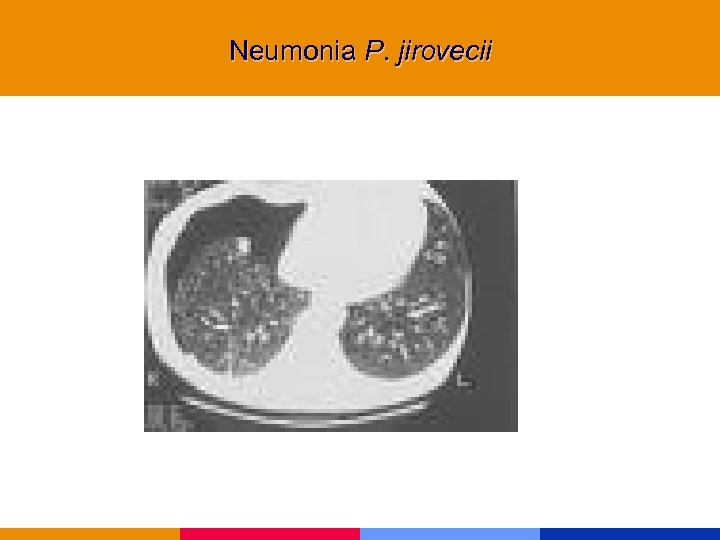

Neumonía por Pneumocistis jirovecii

Neumonía por Pneumocistis jirovecii

Neumonía por Pneumocistis jirovecii § CD 4 < 200 mm 3 § Comienzo insidioso: fiebre, tos seca, disnea. Hallazgos al examen físico incaracterísticos. § Lab: VSG: 50 mm. LDH, valor diagnóstico y pronóstico. Hipoxemia. § Rx infiltrado intersticial difuso, neumatocele, neumotórax. § TC de alta resolución.

Neumonía por Pneumocistis jirovecii § CD 4 < 200 mm 3 § Comienzo insidioso: fiebre, tos seca, disnea. Hallazgos al examen físico incaracterísticos. § Lab: VSG: 50 mm. LDH, valor diagnóstico y pronóstico. Hipoxemia. § Rx infiltrado intersticial difuso, neumatocele, neumotórax. § TC de alta resolución.

Neumonia P. jirovecii

Neumonia P. jirovecii

Neumonia P. jirovecii

Neumonia P. jirovecii

Neumonia P. jirovecii

Neumonia P. jirovecii

Neumonia P. jirovecii

Neumonia P. jirovecii

Neumonia P. jirovecii

Neumonia P. jirovecii

Neumonia P. jirovecii

Neumonia P. jirovecii

Neumonia P. jirovecii

Neumonia P. jirovecii